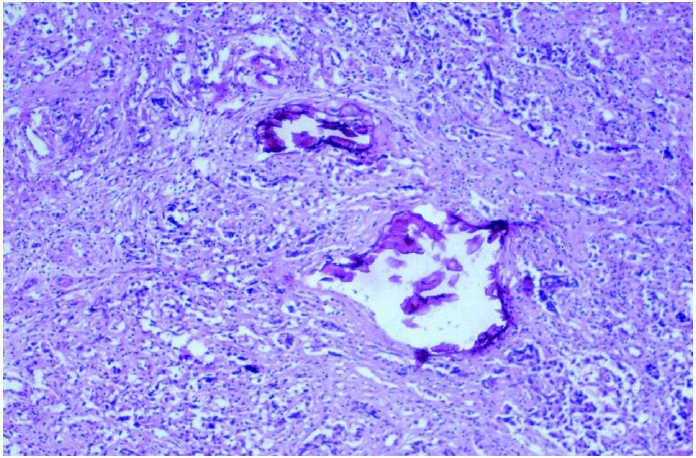

En la sección del ovario derecho se observa que es una tumoración de superficie de corte homogéneo, aspecto edematoso y brillante, en el que no se aprecian áreas de necrosis o hemorrágicas (fig. 3). Microscópicamente se aprecia que la tumoración se dispone formando nidos y trabéculas separadas por finos ejes de tejido conectivo (fig. 4). A mayor aumento, estos ejes conectivos contienen abundantes linfocitos maduros. En el disgerminoma se poduce una importante reacción inflamatoria (fig. 5), mientras que las células tumorales muestran un tamaño medio-grande con un citoplasma bien delimitado y tinción clara, los núcleos son redondos y presentan nucléolos llamativos y cromatina desarrollada (fig. 6).

Figura 5.Estroma infiltrada por linfocitos en el disgerminoma.